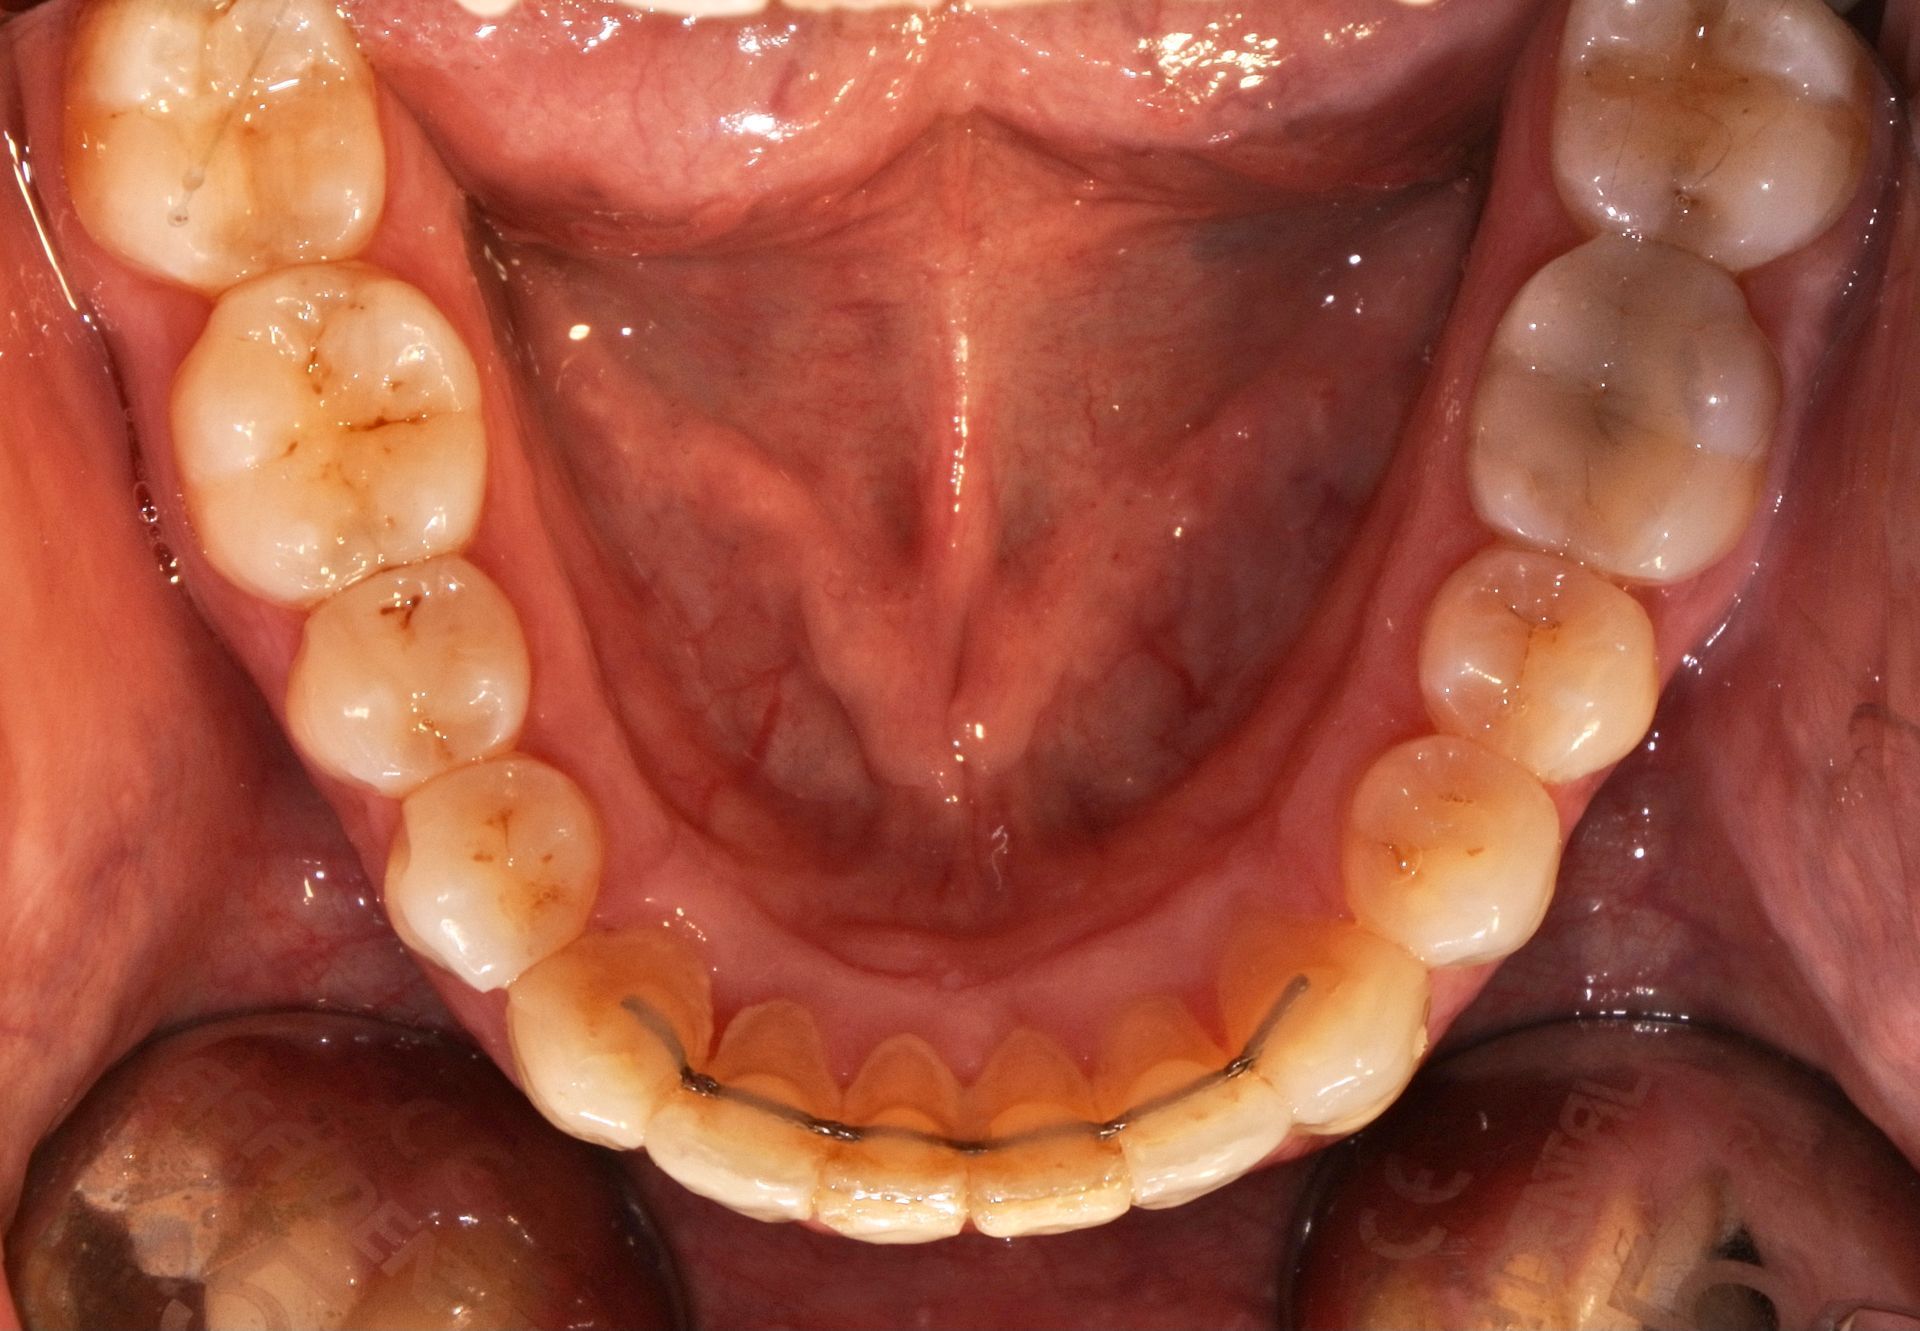

INVISALIGN è un sistema di mascherine trasparenti (aligner) studiato per permettere una elevata predicibilità dei movimenti dentali e della durata del trattamento.

Si tratta di una soluzione invisibile ed efficace per l'allineamento graduale dei denti.